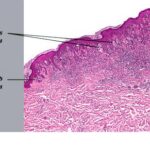

Unlike ordinary nevi and melanomas, melanocytic cells in Spitz nevi are large—often twice the size of epidermal basal keratinocytes, with prominent mononuclear or multinucleated giant cells in the epidermis and/or dermis . Mitoses, usually few in number, are detected in one-half the cases, whereas atypical mitoses are uncommon in Spitz nevi. In contrast to melanoma, the melanocytic cells in Spitz nevi show progressive maturation with increasing depth, becoming smaller and more similar to ordinary nevomelanocytes, with the overall distribution of cells in the dermis being wedge-shaped, with narrowing of the wedge toward the subcutaneous fat.

Melanocytic elements are usually arranged in well-circumscribed nests, although there may be permeation of the epidermis by single cells or small groups of cells. In those cases with epidermal nests, artifactual clefts are usually seen above the nests in half the cases, a finding rarely observed in melanoma. The epidermis is usually hyperplastic, with elongated and bulbous pegs and knobs extending into the dermis, although thinning and even ulceration may occur rarely. The dermal inflammatory cell infiltrate may be slight or marked, band-like, and mainly at the base or patchy around blood vessels and/or intermixing with tumor cells. Although melanin was observed in all 13 patients originally described by Spitz, more recent studies have determined that melanin was moderate in 10 percent of cases and heavy in 5 percent.88